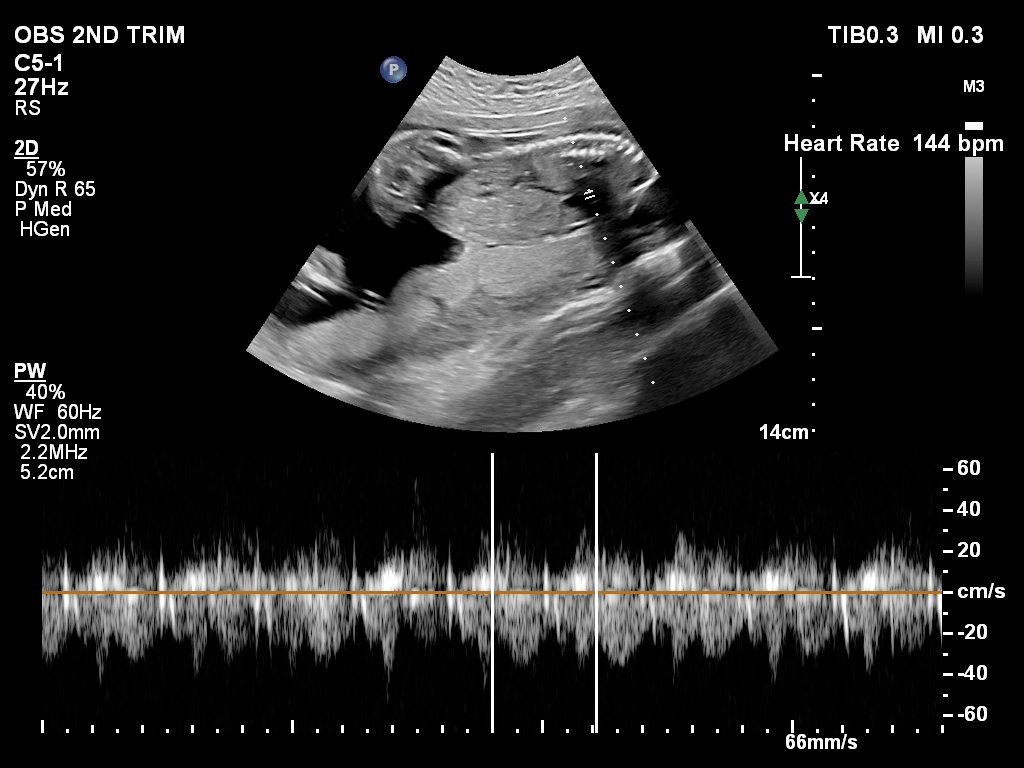

🔹 Fetal Echo / Adult Echo (Echocardiography)

Echo (Echocardiography) is a specialized ultrasound used to examine the heart. Fetal Echo evaluates the baby’s heart structure and function during pregnancy, while Adult Echo checks heart health in adults. It helps detect congenital heart defects, valve problems, and blood flow issues. If you need a fetal echo in Kathmandu, this test plays a vital role in early diagnosis and treatment planning.